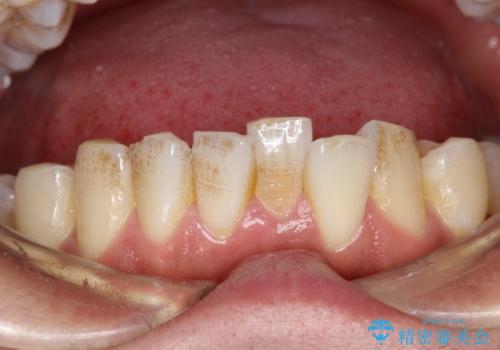

タバコのヤニを取って歯を白くしたい

- タバコを吸われる方で、ヤニを取って歯を白くしたいとのことでした。

歯の表面についた汚れがかなり頑固な汚れだったため、PMTC(エアフロー)の60分コースにて施術しました。

ヤニは歯につくと表面がざらざらしたような舌触りになります。

ざらざらしたところに歯石や茶渋の汚れプラークなどが付きやすいため

タバコを吸われる方は見た目が気にならない方でも歯周病や虫歯の予防としてクリーニングを行うことをお勧めします。